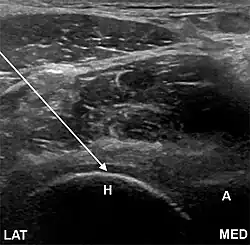

- The anterolateral approach, with the ultrasound probe oriented axially and the femoral head and acetabular rim in view. This often shortens the distance from needle skin entry to joint compared to the longitudinal approach making it a useful approach in larger patients. The introduced needle remains lateral to the femoral neurovascular bundle, and the needle is advanced until its tip rests on the femoral head.

- A low-frequency curvilinear probe (5-2 MHz), coated with a glue sterile dressing table, is put in a transverse plane parallel to the inguinal ligament and utilized to recognize the femoral artery and vein over the hyperechoic femoral head. The probe is then transferred laterally to just over the hyper-echoic femoral head and rotated into an oblique sagittal place so the probe mark is targeted towards the umbilicus.

- Needle insertion and shot . A shallow wheal of local anesthetic is set in the stage of needle entrance. A 6 tsp mix of 5ml of bupivacaine 0.5percent and 1ml of 40 mg/ml of triamcinolone is put in a 10cc syringe. A 20-gauge 3.5 inch regular cutting back spinal needle is directed in-plane under real time ultrasound[4] guidance into the anterior capsular recess. After the needle tip is clearly visualized from the joint area, 1--2 mL aliquots of this solution is gradually injected under reduced pressure. Successful targeting of the joint space is supported by spread of anechoic fluid beneath the iliofemoral fascia inside the anterior capsular recess.